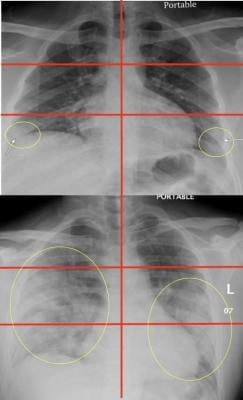

Top image: Chest radiograph of a 23-year-old male with no past medical history who tested positive for COVID-19 via RT-PCR and was subsequently discharged from the emergency department with home care and isolation precautions. Portable CXR shows right and left peripheral lower lung zone hazy opacities; total score=2.

Bottom image: Chest radiograph in a 32-year-old overweight (BMI=30) COVID-19 positive male with a history of childhood asthma who was subsequently admitted and intubated in the ICU for 3 days. Portable CXR shows opacities in all three right lung zones and in the left middle and lower lung zones; total score=5. Image courtesy of Mount Sinai Health System

Investigators focused on every patient's chest X-ray to examine patterns of coronavirus in their lungs, looking at the opacities (white circular markings associated with COVID) and where those patterns lay. Researchers divided the X-rays into six zones (upper right, upper left, middle right, middle left, lower right, and lower left) and developed a scoring system from zero to six to quantify severity. The total score depended on how many zones disease showed up in. Lower severity scores ranged from zero to two, and higher severity from three to six.

Of the 338 patients, 145 were admitted. Patients with highest chest X-ray scores were 6.2 times more likely to require hospitalization, and 4.7 times more likely to be intubated. A more specific breakdown showed that of the 34 patients with a "zero" score, two were intubated; out of the 15 patients with a "one" score, one was intubated; 38 patients had a score of "two," and six were intubated; of the 14 patients with a score of "three," two were intubated; out of 32 patients with a score of "four," 10 were intubated; for the seven patients with a score of "five," three were intubated, and four of the five patients with a score of "six" were intubated.